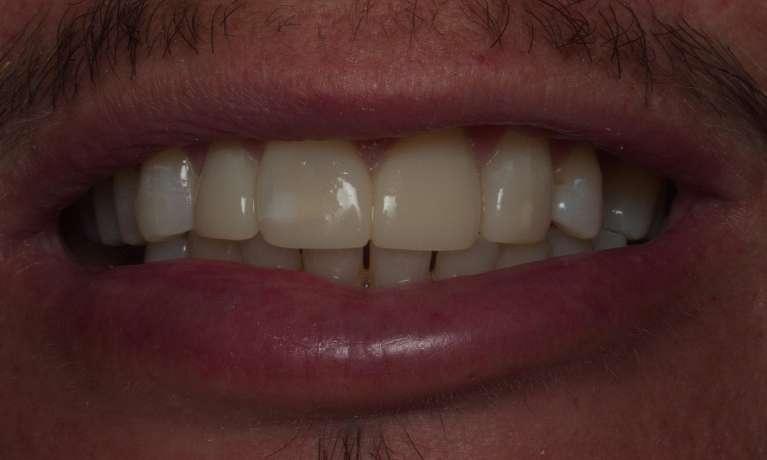

At Springs Family Dental, we know that sometimes cavities happen, and we want you to know that we are here for you and your family. With natural-looking fillings that blend beautifully with your own enamel, we can restore your tooth and its functionality – and nobody will ever know that you’ve had a cavity.

Composite resin fillings are both durable and natural-looking. We'll match the new filling to your tooth’s coloring so they blend together, which means nobody will be able to tell the difference between the two.

With advancements in dental technology and materials, our Colorado Springs dental office can now offer tooth-colored composite resin fillings. Not only do tooth-colored fillings blend in seamlessly with your smile, but they also require less removal of your tooth structure to bond with your tooth.

Our office provides a variety of different filling materials to suit the individual needs of each patient; however, most of these fillings are tooth-colored composite. Composite has many benefits, such as blending naturally with the tooth, bonding to the remaining structure, and acting relatively inert in your mouth.

A tooth-colored filling can also be used in dental bonding—which allows Dr. Michael Terveen to change the size, shape, and shade of your existing teeth.